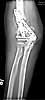

At surgery it appeared infected. Cultures eventually grew out strep viridans subcultured through broth. It was very hyperemic. I treated it with hardware removal, a spanning plate that was meant to provide temporary stability, and irrigation & debridement x 2. (I did not use an external fixator because of the osteoporosis, and the inability to get stability of the fragments.) An antibiotic impregnated cement spacer was added. Files( after I&D.) Last I&D was in March 2004.

after I&D